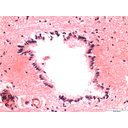

Mammalian Spinal Cord 40X central canal.jpg